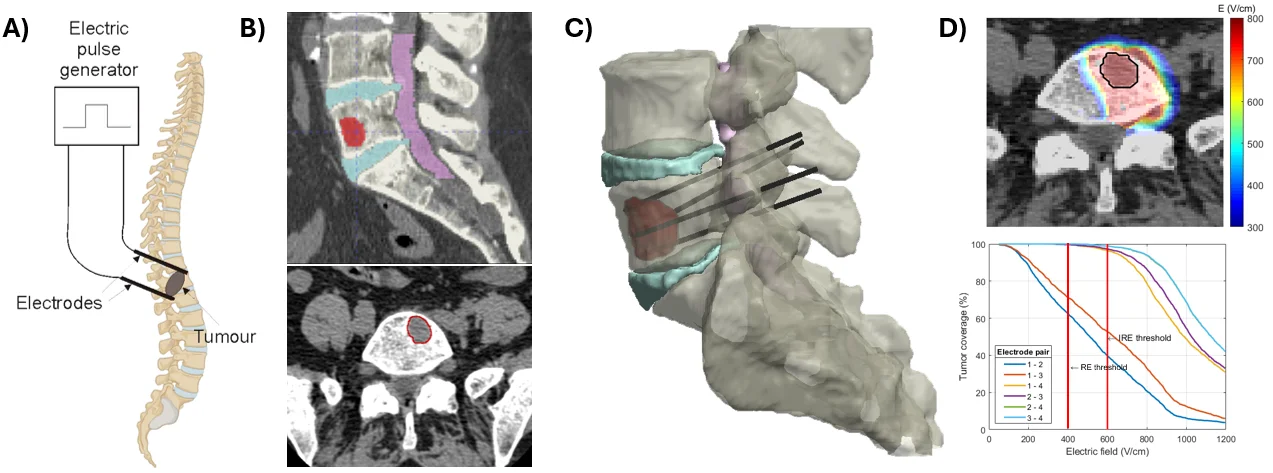

Tailored to each patient's anatomy, computer-assisted treatment planning aims to design a technically feasible plan that optimizes electrode placement and pulse parameters to ensure reliable coverage of the entire clinical target volume (e.g., a tumor with a safety margin) with an electric field exceeding the reversible electroporation threshold for ECT or the irreversible threshold for IRE ablation. At the same time, treatment planning aims to minimize unintended exposure and damage to surrounding healthy tissue and critical anatomical structures, while respecting anatomical and procedural constraints. By integrating patient-specific anatomy with numerical modeling of electric field distributions, treatment planning provides quantitative guidance for clinicians and supports the development of more precise, predictable, and optimized minimally invasive electroporation-based therapies, as illustrated on Figure 5 for percutaneous ECT of a spinal metastasis.

Patient-specific digital twins are built from medical images (CT or MRI), which are segmented to identify target tissues and relevant anatomical structures, and then used to construct three-dimensional, anatomically accurate models. Electrode or catheter geometries are introduced into these models, allowing tissue- and organ-level simulations that provide a macroscopic description of electroporation by computing the resulting electric field distribution in realistic patient anatomy. These models explicitly account for anatomical constraints, tissue inhomogeneities, and clinically feasible electrode placements, which are critical for predicting treatment outcomes in complex, deep-seated targets.

In our research, patient-specific digital twins are used for two main applications: (1) investigating the safety and efficacy of novel clinical applications, such as pulsed field ablation (PFA) for cardiac ablation, and (2) supporting patient-specific treatment planning for minimally invasive treatment of deep-seated tumors with electrochemotherapy (ECT) or irreversible electroporation (IRE) ablation.